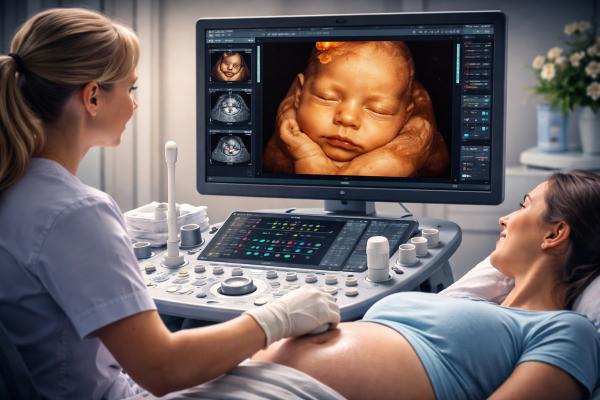

During the Scan

- Calm, private scanning room

- Live viewing on a large display screen

- Gentle and patient-focused approach